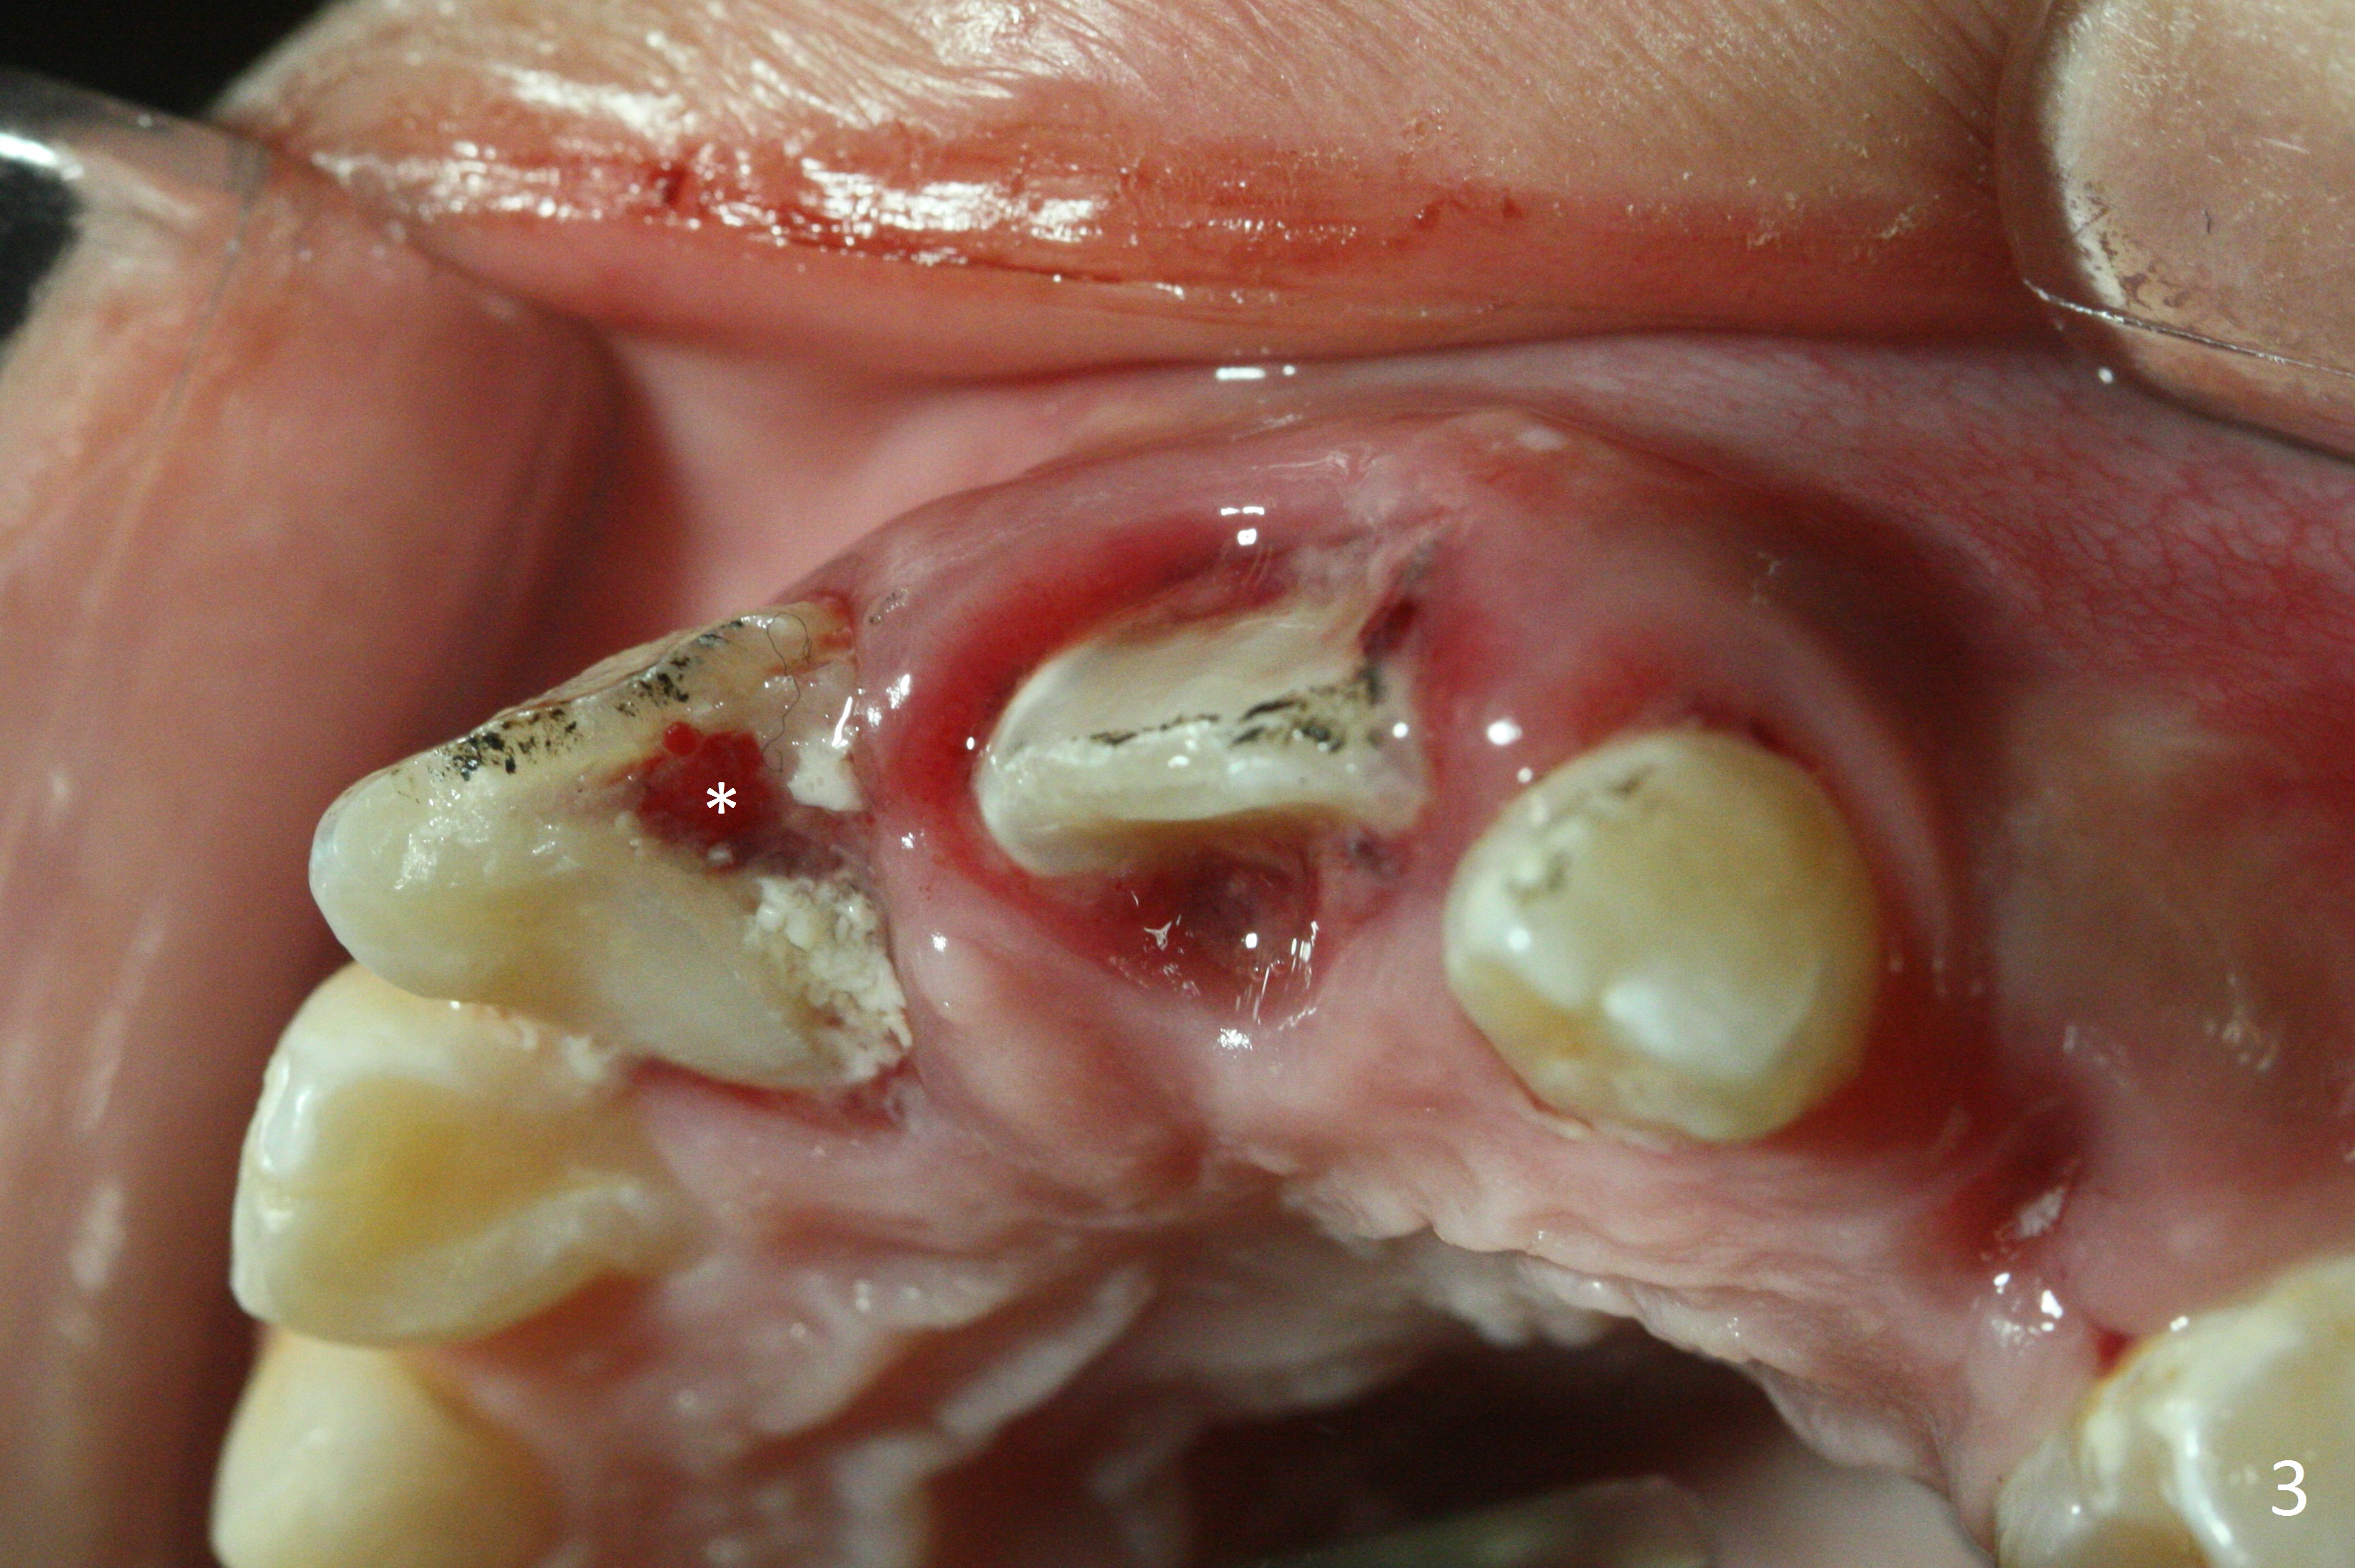

A 10-year-old boy has had Class II Division II malocclusion (Fig.1 impression taken 1 year earlier). He is brought to clinic the 2nd day after a bike accident. The tooth #8 fractures (Fig.2-4) with mesial pulpal horn exposure (Fig.3 *, while #9 intrudes. After debridement of the affected teeth (Fig.5), the exposed pulpal tissue is resected (partial pulpotomy to keep the tooth vital to finish root and apex development) and the pulpal horn is filled by MTA at #8 (Fig.6 *). The tooth #8 is restored with composite (Fig.7 C). Forceps fail to extrude the tooth #9. His parents are reluctant to accept orthodontic extrusion, which is accomplished by Dr. Shaughnessy 2 days later (Fig.8,9). The patient will leave for China in 2 days and will return in a month.